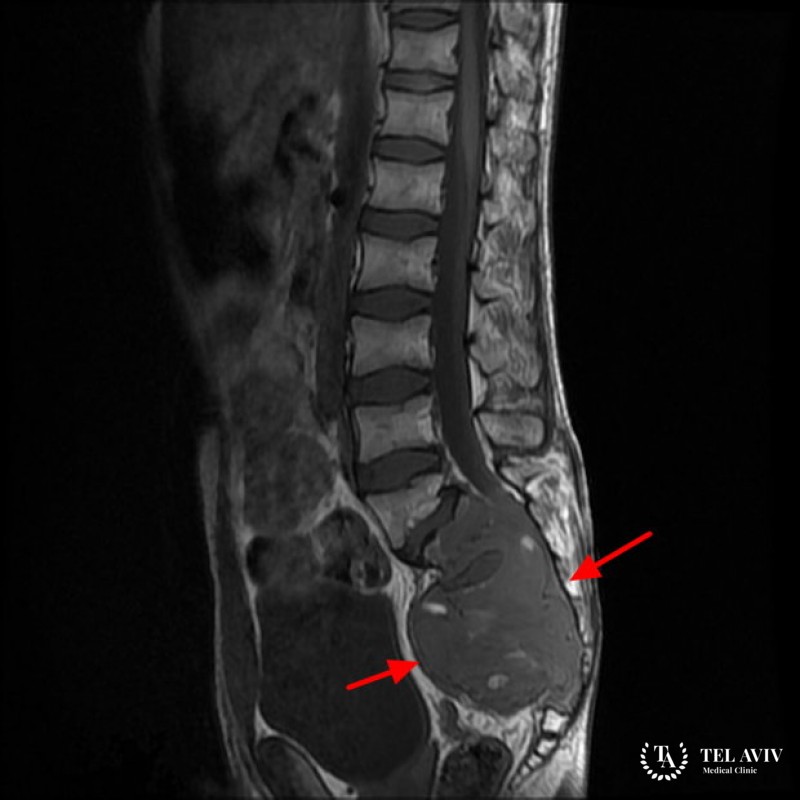

Хордомы относятся к категории опухолей с невыясненной природой. Место локализации патологического образования – черепное основание, крестец, позвоночный столб, прилежащие области. Чаще всего появляется хордома в основании черепа и крестцово-копчиковом отделе.

Поражение крестцовой зоны вызывает слабость в ногах, боли в малом тазу, нарушение координации движений. Тазовые органы ребенка теряют чувствительность, конечности немеют. Хордомы нетипичной дислокации проявляются болевыми ощущениями в местах прогрессирования, неврологическими расстройствами. Для хордомы в запущенной форме характерны следующие симптомы: